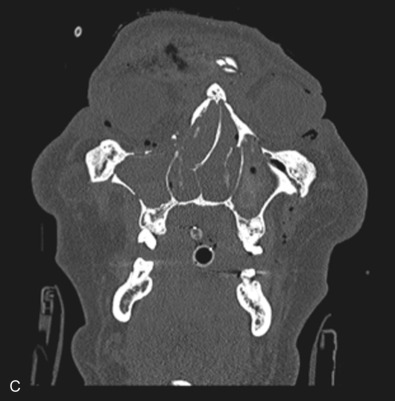

Le Fort III fractures generally consist of a combination of fractures that involve the palatine bones, the maxilla, the pterygoid plates, the nasal bones, lacrimal bone, and zygomas; they essentially separate the face along the base of the skull. The fracture pattern extends through the nasofrontal suture along the medial wall of the orbit, through the inferior orbital fissure and the lateral orbital wall to the zygomaticofrontal suture. In addition, the zygomaticotemporal suture is separated. The fracture extends across the sphenoid bone resulting in dysjunction at the pterygoid plates ( Figs. 1.13.16 and 1.13.17 ). The septum is separated from the cribriform plate of the ethmoid. Pure Le Fort III fractures are rare, and in actuality, most are ZMC fractures in conjunction with Le Fort I and II fractures lending the appearance of a comminuted “Le Fort III.” The force is delivered from the orbital level, resulting in craniofacial dysjunction. The fracture is generally more comminuted and more extensive on the side of force application.